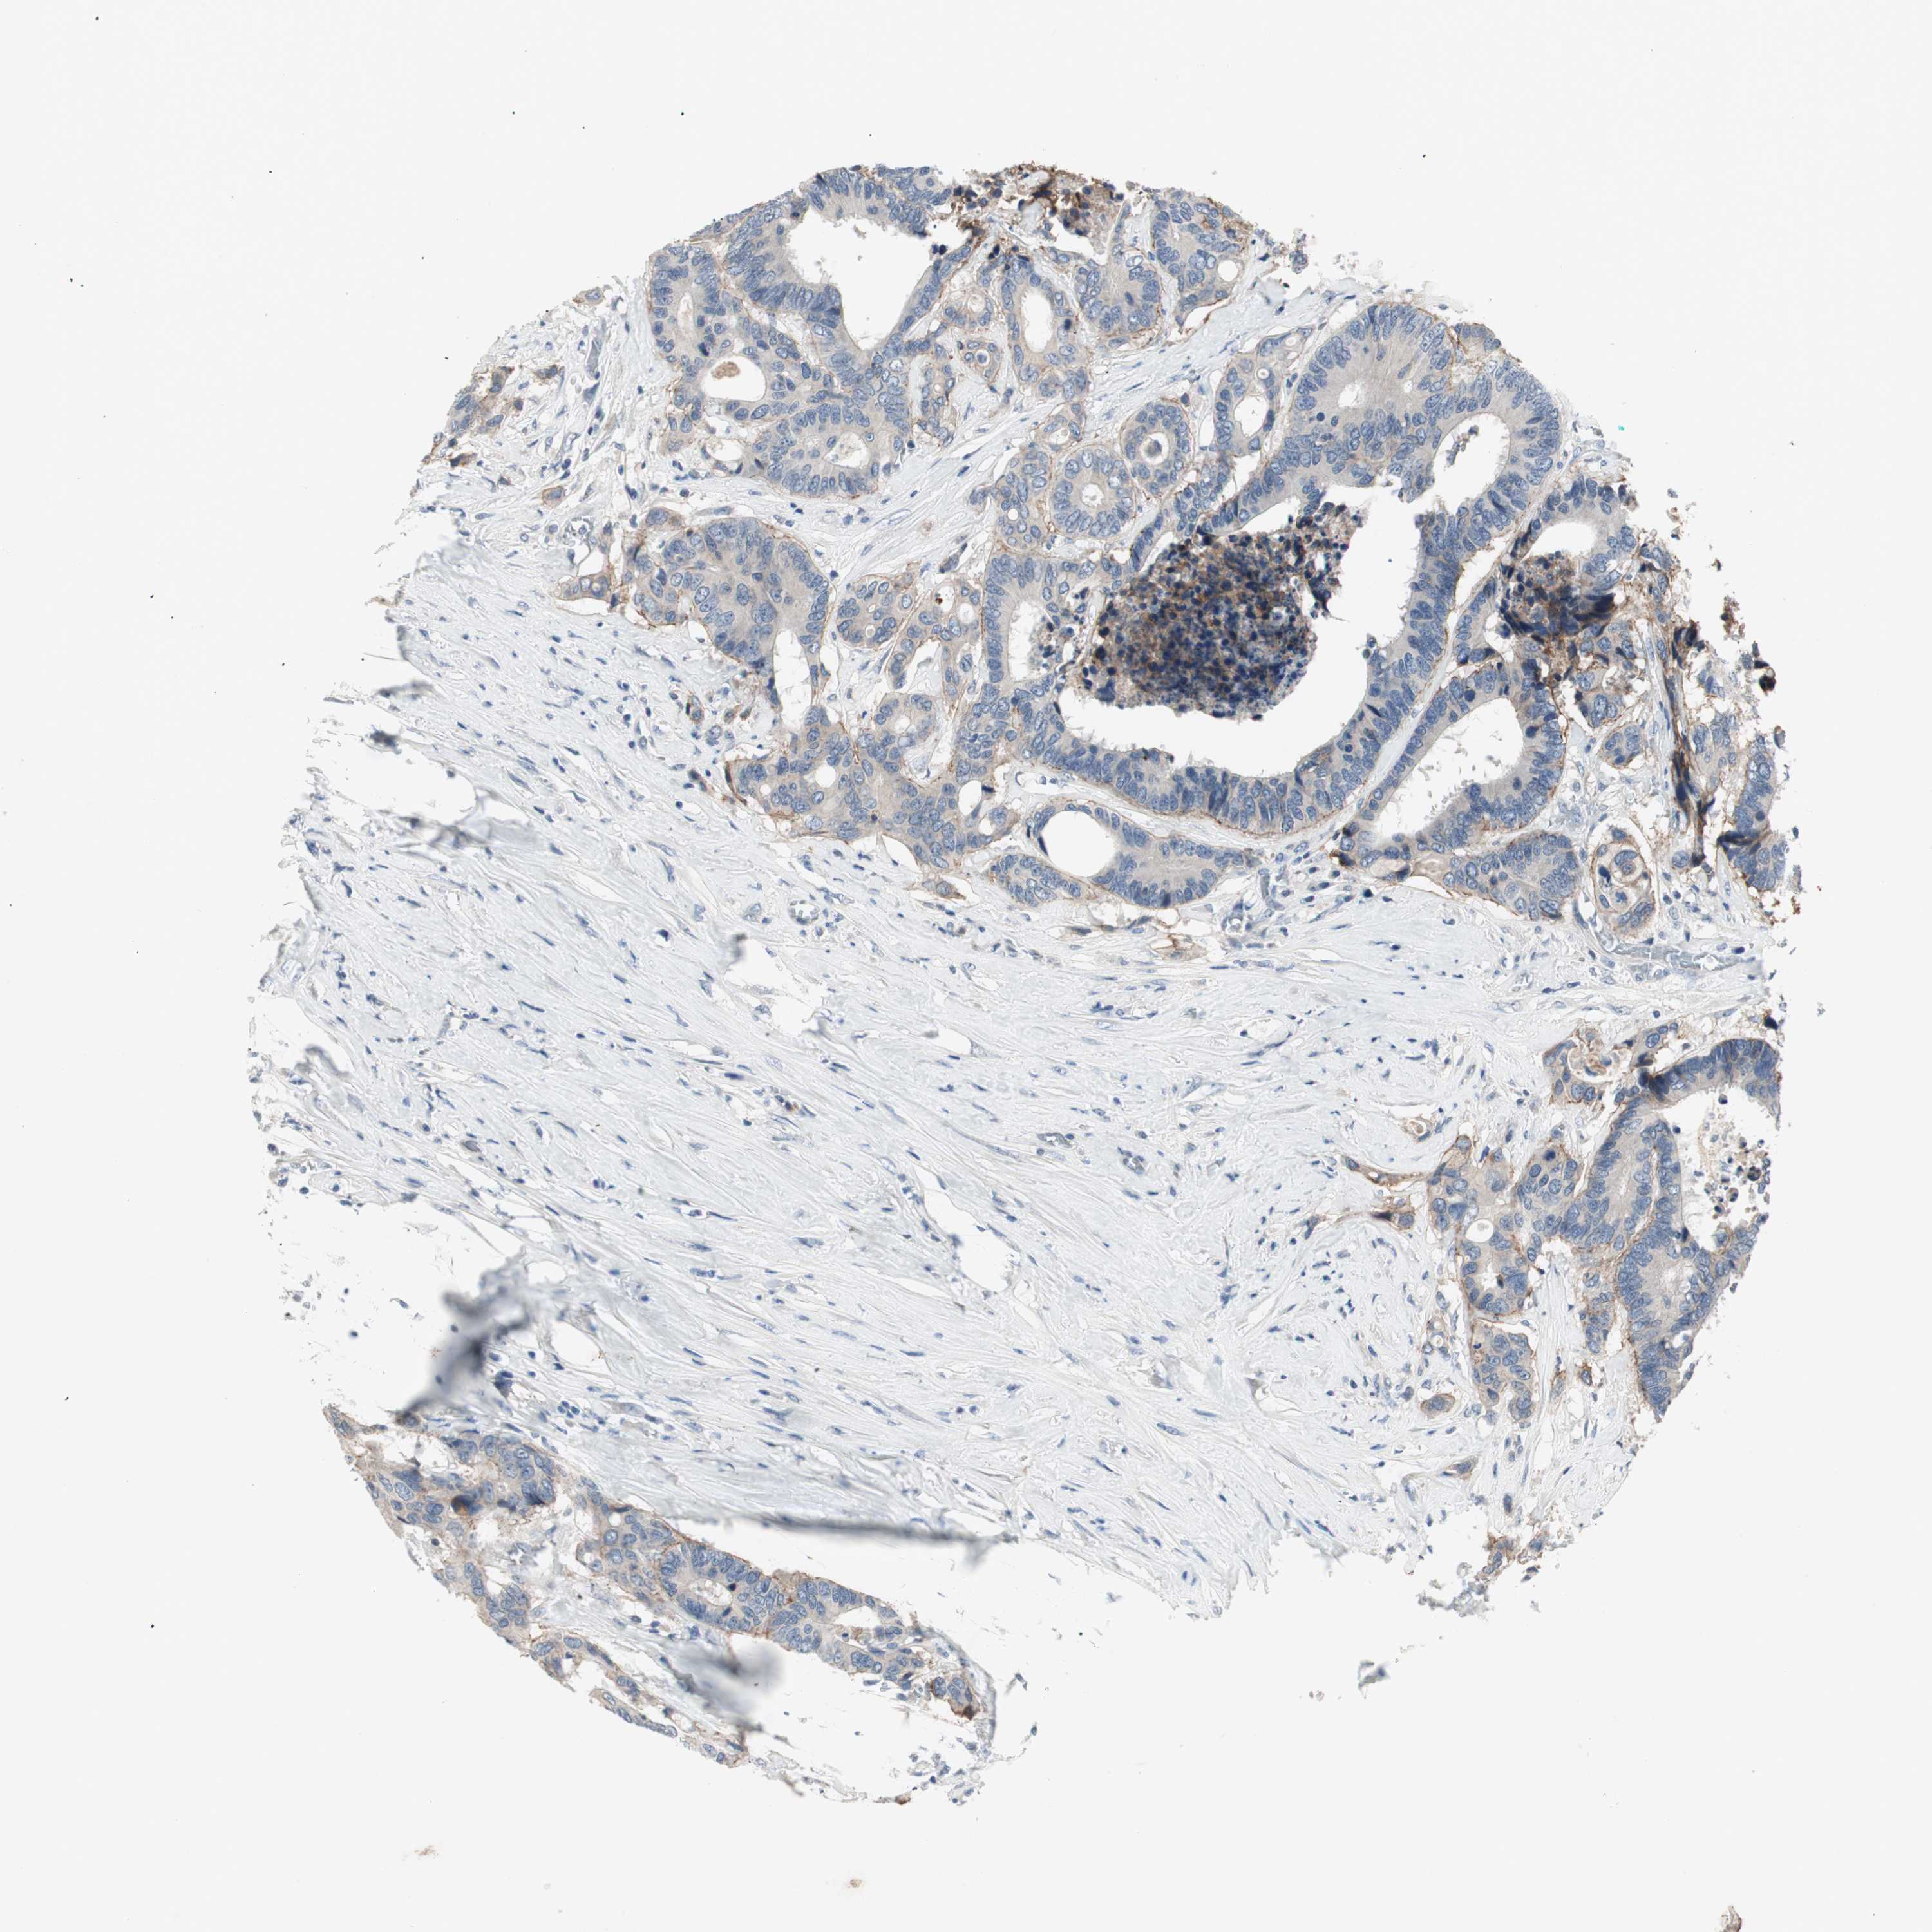

CANCER COLORECTAL CANCER Show tissue menu

Colorectal cancer

Human cancer

Colon adenocarcinoma